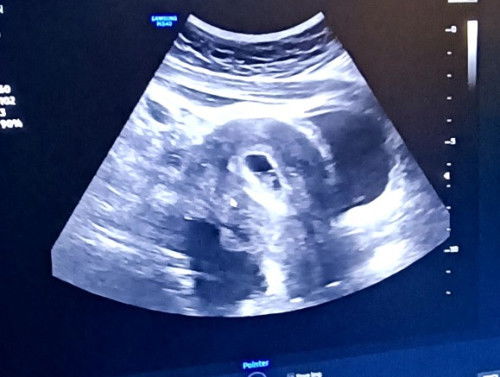

Tadi scan 6w 3days. Ada heartbeat kuat..nmpk kantung janin semua.tp doc nmpk Ada cyst.bahaya tak?

Cyst ni kena rujuk pakar O&G. Jawapan kat sini hanya pengalaman persendirian.

kalo kecik xde masalah...tpi kalo bsr mmg kena operate buang